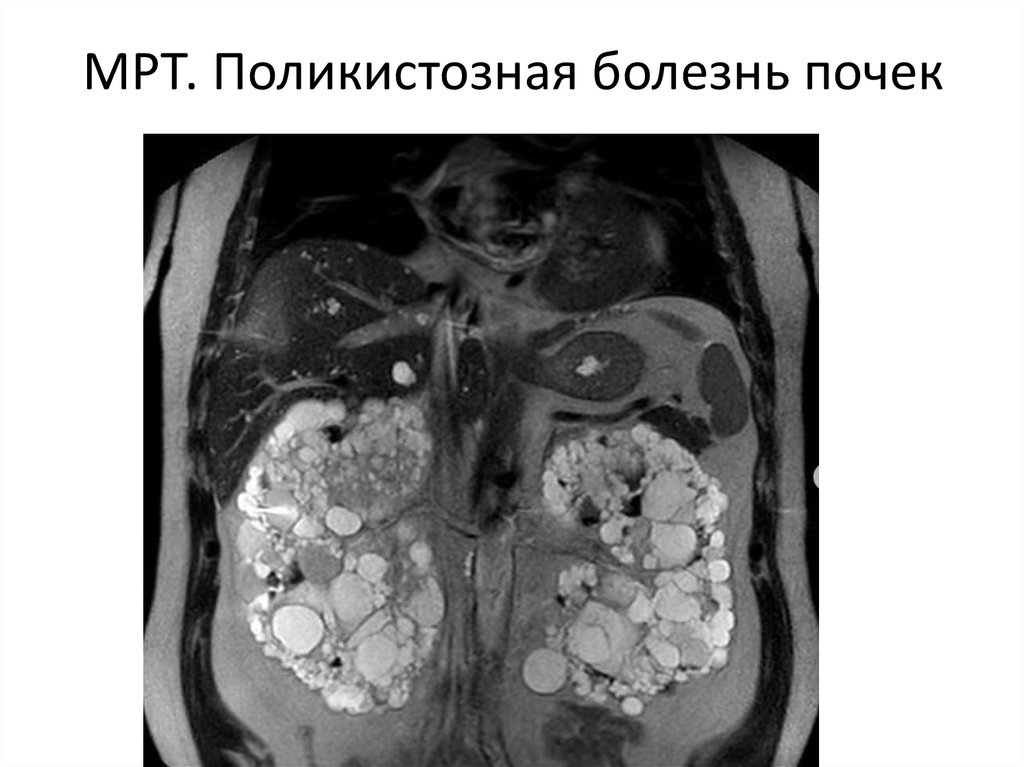

МРТ. Поликистозная болезнь почек